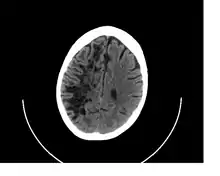

![]() A perivascular space as seen on CT | |

Perivascular spaces are distinguished on an MRI by several key features. The spaces appear as distinct round or oval entities with a signal intensity visually equivalent to that of cerebrospinal fluid in the subarachnoid space.[7][14][15] In addition, a perivascular space has no mass effect and is located along the blood vessel around which it forms.[14]